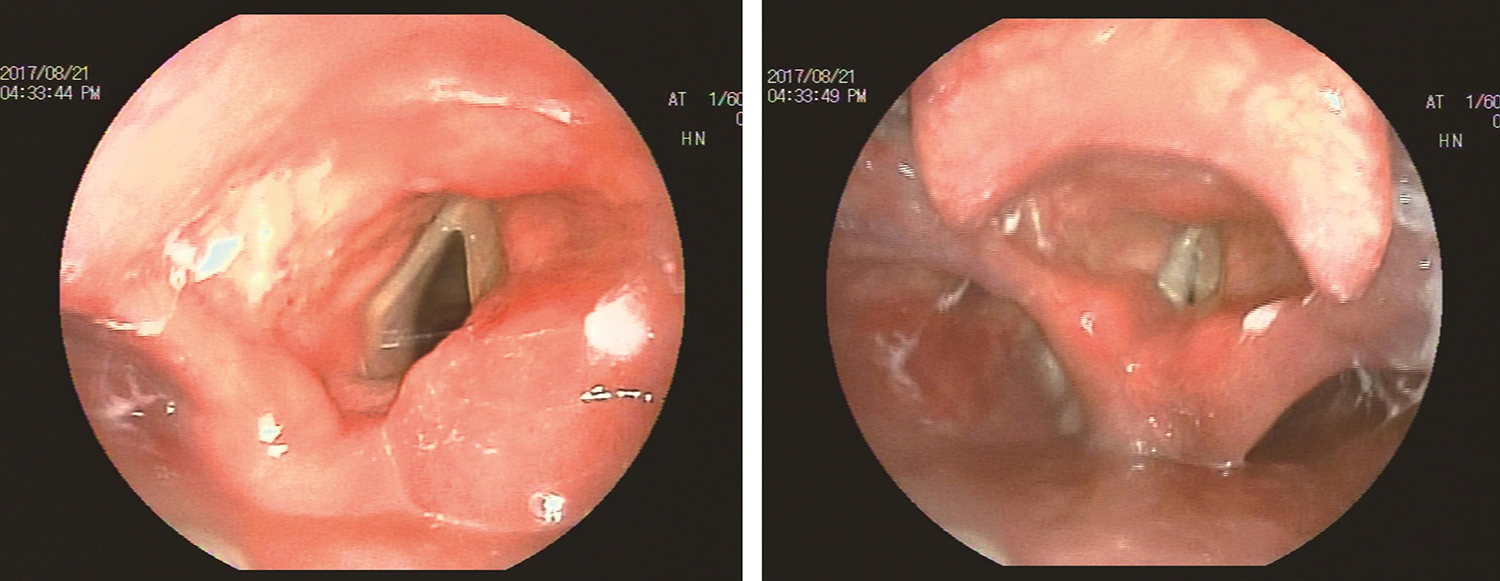

2.电子喉镜检查

(1)2017年8月21日:喉部右侧黏膜、声带轻度肿胀,右侧声带位于旁正中位(图13)。

图13 2017年8月21日复查喉镜

(2)2017年11月23日:右侧声带位于旁正中位,轻微活动,声带闭合时有裂隙(图14)。

图14 2017年11月23日复查喉镜